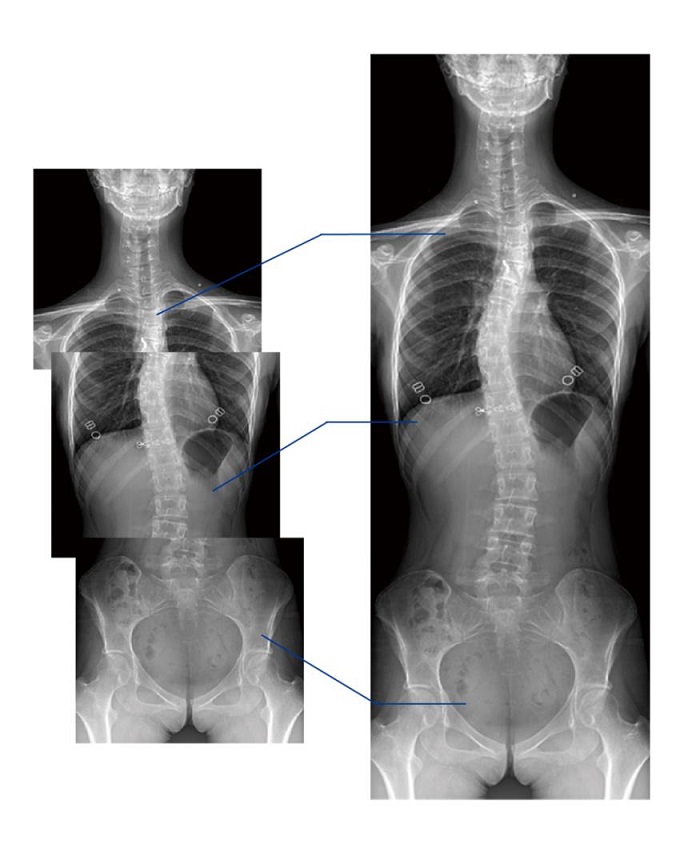

全景拼接功能

全景拼接功能是在全景影像拍攝的情況下,拍攝各個部位的影像,得到的圖像最終合成一幅全景圖像。適用于輔助脊柱畸形矯形治療、康復(fù)檢查,可對脊柱、下肢及下肢靜脈造影進(jìn)行分段攝片,然后對分段圖像進(jìn)行拼接,在一幅X光圖像上完整顯示全脊柱或下肢整體形態(tài),為臨床提供高精度圖像。